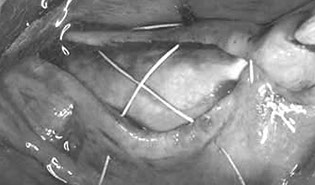

This regenerative course focuses on barrier membrane particulate bone grafts. The volume of bone and related procedures covered in this course is for appositional augmentation. The game changing Versah bone drilling system is demonstrated to treat ridges effectively and avoid the need for grafting in the correct circumstances. Bone grafting materials – alloplasts, allografts and the use of autologous blood draws for Autologous Stem Cell Harvest and manufacture of advanced platelet rich fibrin (A-PRF), injectable platelet rich fibrin (i-PRF) and the use of fibrin glue. Advanced surgical techniques of tissue release (Soft Brushing) and advanced surgical site closure techniques are presented in detail along with bone physiology and metabolism. Indications for extraction and immediate implant insertion, esthetic complication of implant position and angulation are also covered in detail.

Perform the procedures of site preparation to membrane fixation, autologous bone harvesting, layered graft placement and suture closure

in pig’s head laboratory